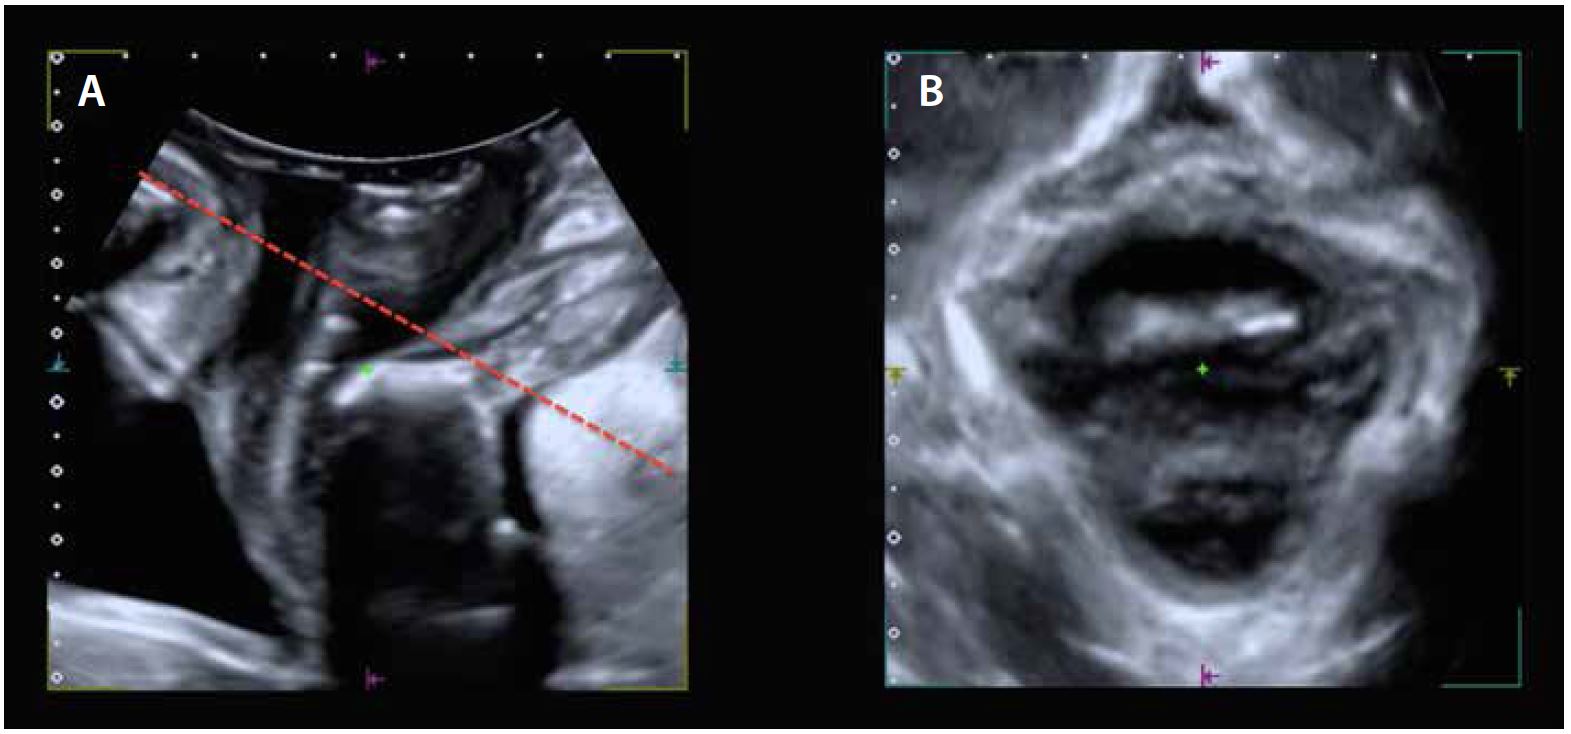

Аксіальне дослідження LAM зосереджено на площині мінімальних розмірів діафрагми, обмеженої області в його передній частині та каудальною частиною лобкового симфізу, а в його задній частині — аноректальним кутом, акцентованим центральною частиною LAM (мал. 3A). Тривимірне ультразвукове дослідження тазового дна дозволяє візуалізувати аксіальну площину, дозволяючи оцінити LAM та урогенітальний гіатус (мал. 3B).

3D ультразвукове дослідження виконується датчиками з кутом сканування 85° (для отримання повного об’єму LAM). Об’ємне обстеження складається з трьох ортогональних зображень і «відтвореного зображення» (напівпрозоре представлення вокселів із визначеної зони інтересу). Виконання 4D дослідження дозволяє проводити динамічну оцінку тазового дна в реальному часі.

На Малюнку 3. Зображено орієнтир площини мінімальних гіатальних розмірів (червона лінія), яка визначається каудальною частиною лобкового симфізу та аноректальним кутом (A). Площина мінімальних гіатальних розмірів (В)